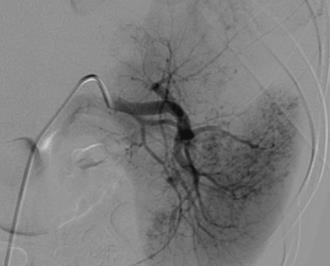

弹簧栓子异位:是指弹簧栓子释放靶血管附着区偏离,主要包括3个原因

除了将异位的弹簧栓子取出,在有些情况下可以考虑将异位的弹簧栓子推向末段(Push coil in further)或接受异位弹簧栓子现在的位置(Accept situation),但先决条件是不能造成器官功能的损伤。 弹簧栓子导管内崁顿(Coil stuck in catheter) 主要原因 • 弹簧栓子/导管不匹配 (Mismatch coil / catheter) • 弹簧栓子“粘” 在导管内(Coil “glued” in catheter) 解决方法 • 避免弹簧栓子/导管不匹配( Avoid mismatch coil / catheter) • 每个弹簧栓子释放后都冲洗导管 (Rinse catheter with saline after every coil) • 用1毫升注射器将弹簧栓子冲出导管(Flush out coil with (1 ml. Luer-lock) syringe) • 弹簧栓子崁顿发生后,取出导管重新插入(Remove catheter / re-catheterize) 总结